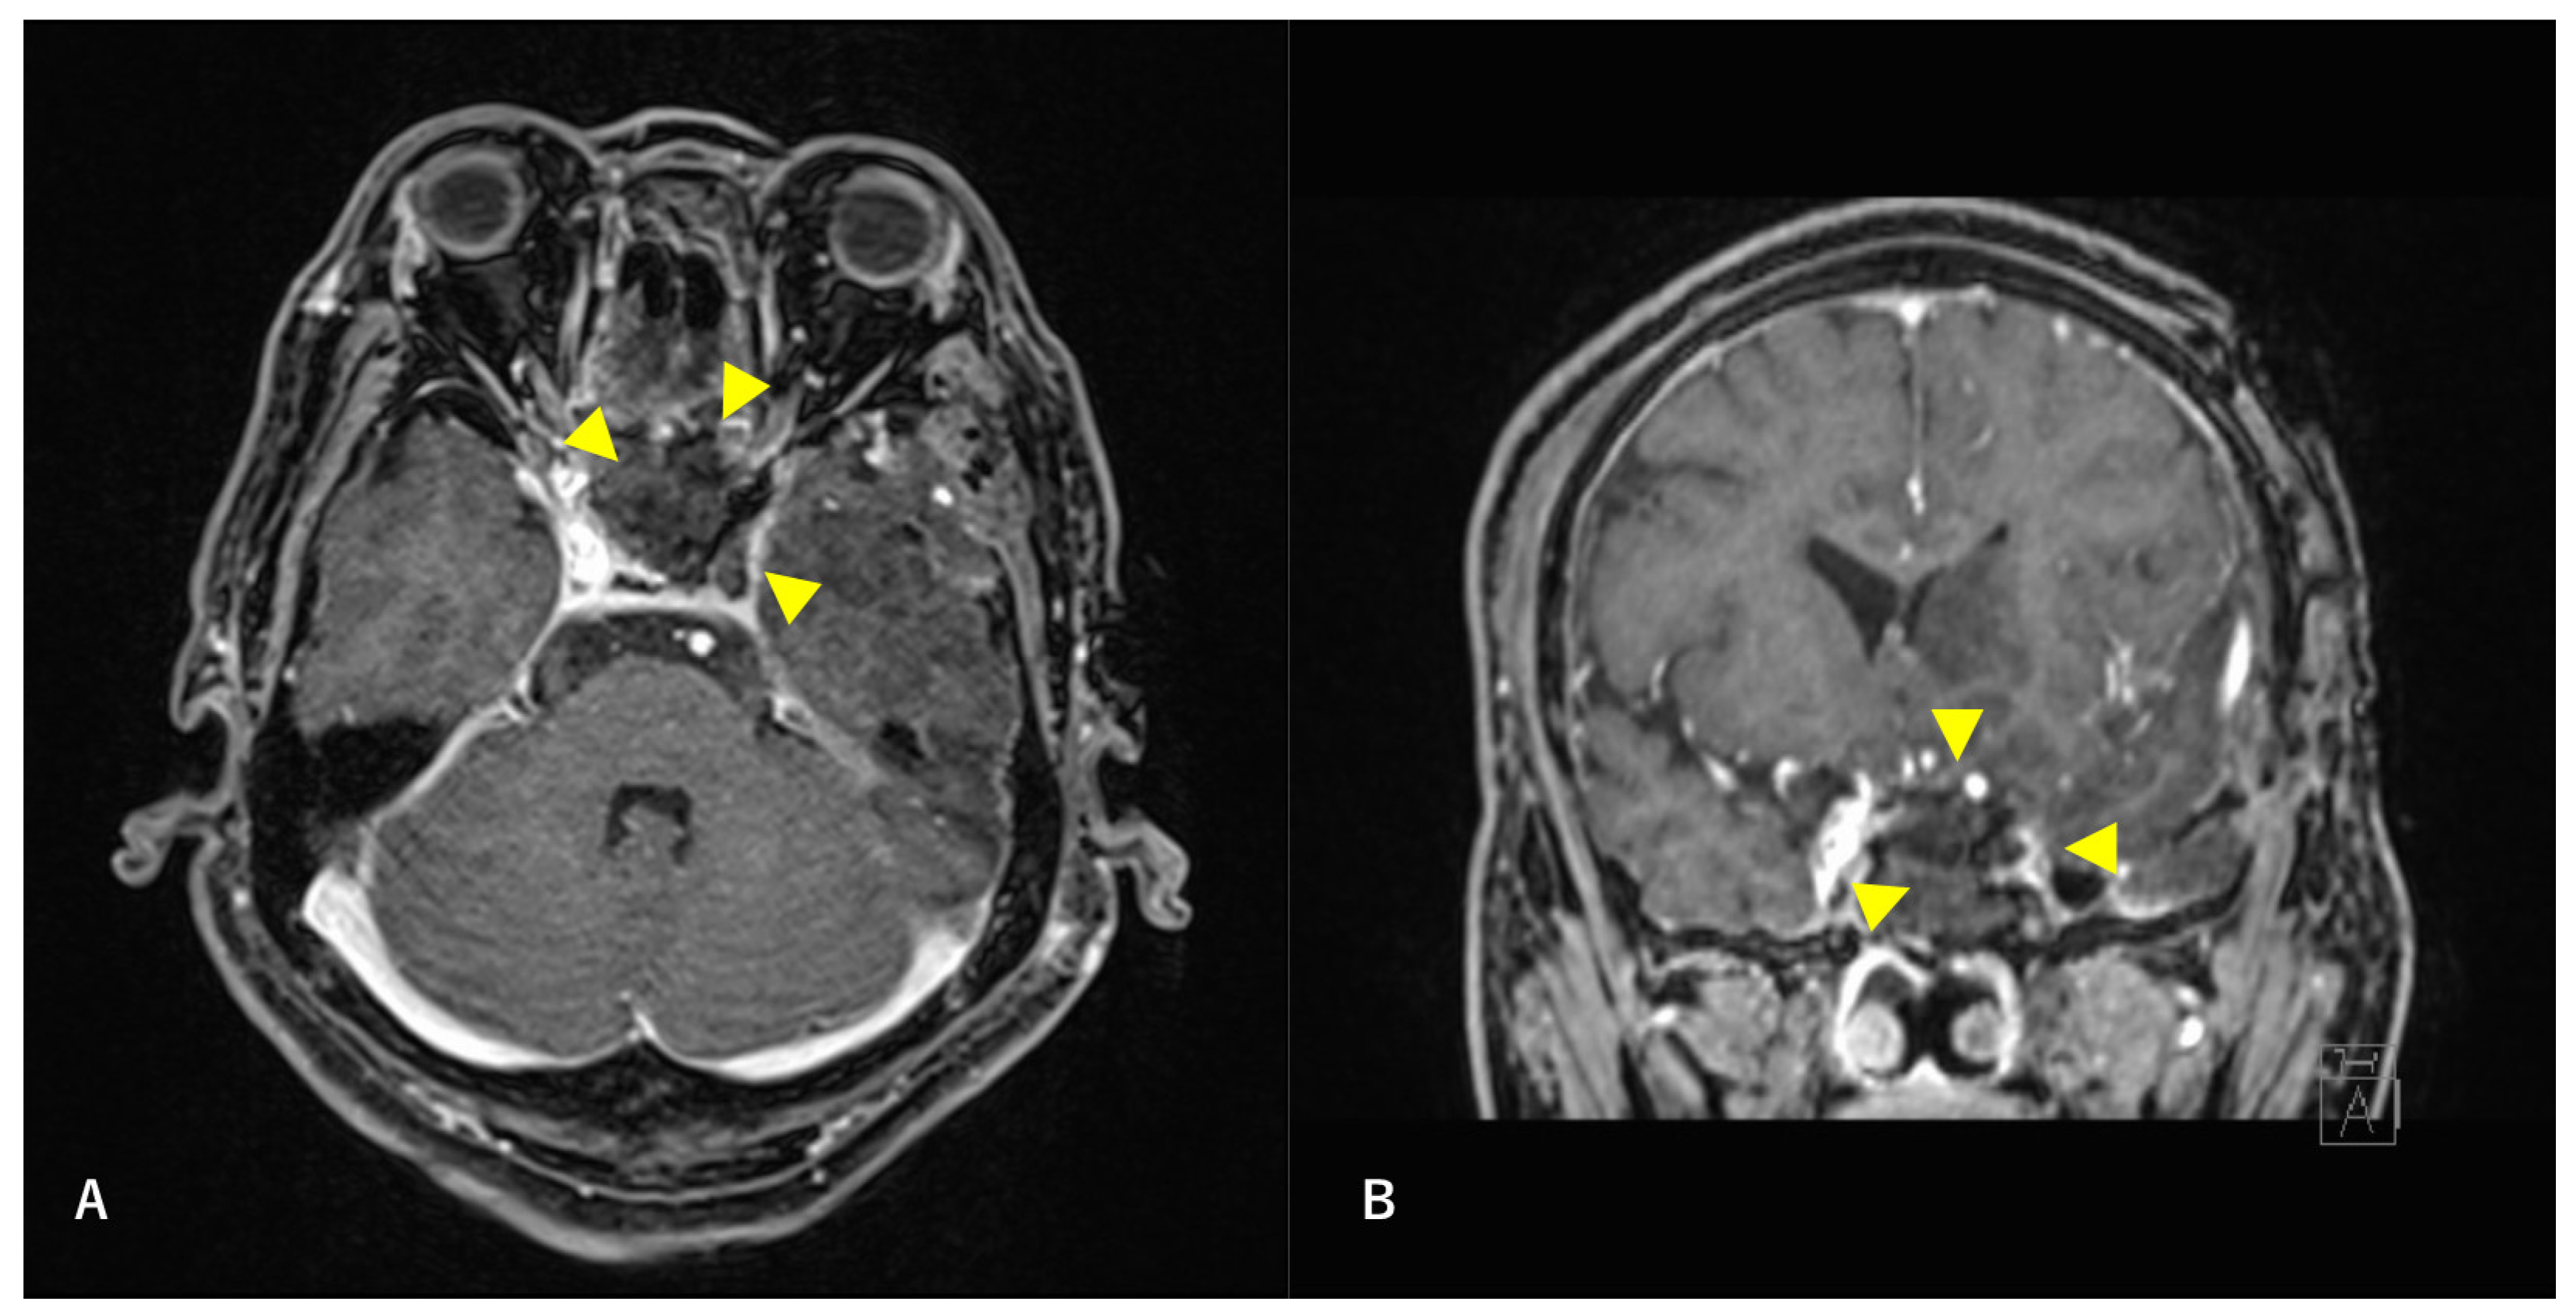

Figure 2. Preoperative T2-weighted magnetic resonance image (MRI) findings. Axial section (A) and coronal (B) images are shown. A high-intensity mass is observed in the left sphenoid sinus. The ICA is surrounded by a mass. Arrowheads indicate tumors.

Figure 4. Postoperative T1-weighted contrast-enhanced MRI findings. Axial section (A) and coronal (B) images are shown. The tumor is confirmed to be resected along with the ICA. Arrowheads indicate the site of tumor removal.

A multidisciplinary team of otolaryngologists and neurosurgeons performed a complete resection of the tumor using a simultaneous combined transcranial and transnasal approach that utilized high-flow radial artery bypass between the M2 segment of the left middle cerebral artery (MCA) and the left cervical external carotid artery with an additional superficial temporal artery–MCA bypass. The margin of tumor resection was determined by a rapid intraoperative diagnosis to confirm the tumor extent. The ICA was trapped under blood flow preservation bypasses, enabling complete resection of the tumor along with the ICA (Figure 4). The ocular artery and cranial nerves III–VI were preserved. The skull base was reconstructed using two layers of the temporalis muscle and a vascular pedicle nasoseptal flap. Magnetic resonance angiography was performed immediately after the surgery, indicating adequate blood flow through the bypasses (Figure 5). The postoperative immunohistochemistry results were positive, similar to the biopsy immunoprofile (Figure 6). In addition, there were no S-100 protein-positive sustentacular cells around the tumor cells. Differentiating between high-grade ONB and neuroendocrine tumors is sometimes difficult; the tumor was eventually diagnosed as NEC, based on the absence of sustentacular cells and the absence of morphological findings such as Homer–Wright rosettes (Figure 6D).